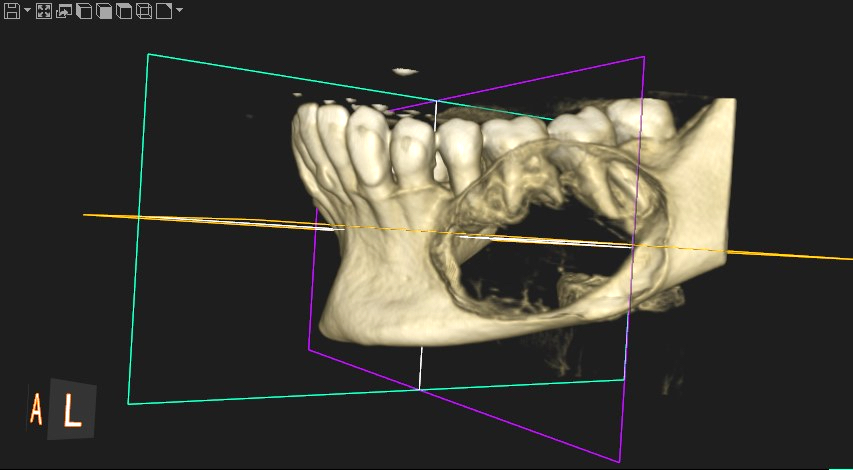

Radiology description

- Radiological findings vary according to maturity of lesion; early lesions show well defined corticated radiolucency and over time, lesion becomes progressively more radiopaque (Heliyon 2021;7:e07594, BMJ Case Rep 2020;13:e239286)

- Well circumscribed, unilocular lesion with centrifugal pattern of growth (Heliyon 2021;7:e07594)

- Can present as lesion with well defined sclerotic borders and is predominantly unilocular (BMJ Case Rep 2020;13:e239286)

- Larger lesions show expansion, thinning and perforation of buccal and lingual cortex and involvement of the lower border of mandible (BMJ Case Rep 2020;13:e239286)